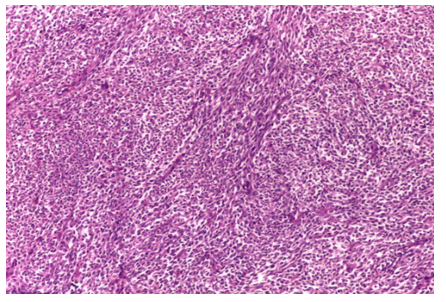

During the exam, we found a firm, non-painful, fixed mass in the front-inner part of her right thigh, measuring roughly 5 x 4 cm. The skin over the mass looked normal, and there were no swollen lymph nodes nearby. Blood tests, including a full blood count and markers of inflammation, came back normal. An MRI scan showed a 5.2 x 4.1 x 3.8 cm mass with uneven borders and mixed characteristics, pointing to a possible cancerous soft tissue tumor.

Figure 1: MRI Scan (T2-weighted MRI (coronal view) of the lower pelvis and thighs)

Description:   5.2 x 4.1 x 3.8 cm mass in the right thigh with an  irregular oval shape, showing a mix of bright white (hyperintense) and darker gray (hypointense) areas, suggestive of a malignant soft tissue sarcoma. A black arrow points to the mass, confirming its size matches the measurements. The white arrow highlights a winding, high-flow blood vessel feeding the tumor. The surrounding muscle tissue looks medium gray, while the femur appears dark (low signal). The left thigh, shown for comparison, has normal muscle and bone structure.

Soft tissue sarcomas in children are a diverse group, and spindle cell sarcomas are a rare type within this category. The MRI (Figure 1) revealed a mass with uneven borders and mixed signal patterns, which is typical for cancerous soft tissue tumors and helped guide the decision to biopsy and operate. Under the microscope, the tumor showed spindle-shaped cells, frequent cell division, and areas of tissue death, all signs of an aggressive cancer that needed quick action [2]. The microscopic images (Figures 2 and 3) highlight the spindle cell structure, with Figure 2 showing a few dividing cells and Figure 3 emphasizing the dense, bundled cell arrangement. The lack of visible cell division or dead tissue in Figure 3 is likely due to differences in the sampled area, as tumors can vary across sections. The surgical specimen (Figure 4) reveals a tumor with bloody and fibrous areas, matching the aggressive nature of high-grade sarcomas. Special staining was key in ruling out other tumors like rhabdomyosarcoma, which was excluded due to the lack of myogenin staining and only focal desmin positivity, and synovial sarcoma, which was less likely due to the absence of epithelial markers and the overall staining pattern [3]. The positive outcome here highlights the importance of removing the tumor with clear margins and using additional treatments like chemotherapy, as recommended by current guidelines [4].